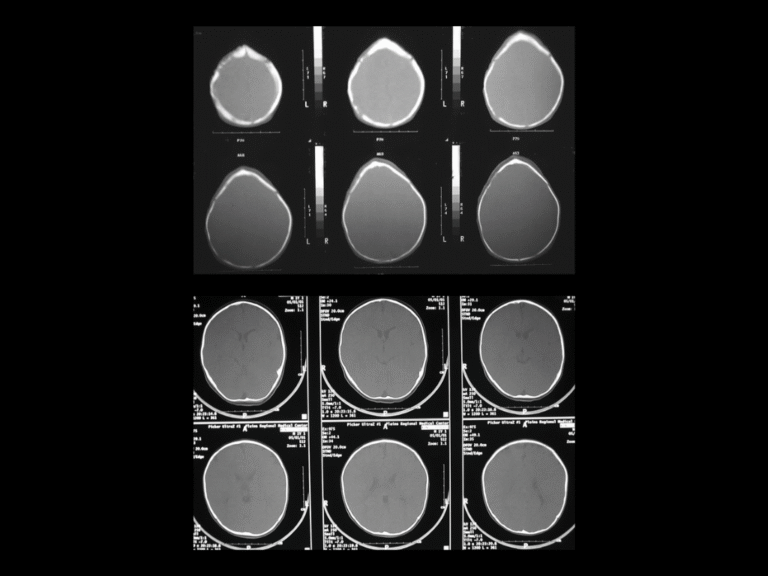

Endoscopic-assisted craniosynostosis surgery is a minimally invasive technique developed to treat infants diagnosed within the first few months of life. Introduced more than two decades ago, this approach allows for safe and early correction of abnormal skull growth by releasing the fused suture through small incisions.

The principle behind the endoscopic method is to use the natural, rapid growth of the infant brain to reshape the skull once the restriction is released. Because the incisions are small and the bone removal limited, this method reduces surgical time, blood loss, swelling, and hospital stay compared to open cranial vault reconstruction.